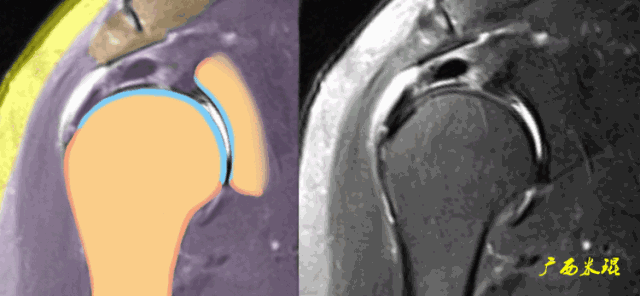

肩袖损伤的MRI分级(Zlaikin)

Grade0:肩袖形态正常,连续性完好,肩袖信号正常。

Grade1:肩袖形态正常,连续性完好,肩袖内信号异常。

Grade2:肩袖连续性存在,形态异常(肩袖变薄/变厚,形态不规则)。

Grade3:肩袖外形异常,连续性中断。

在Zlaikin分级中,0级是正常肩袖,1、2级代表退变,3级为撕裂,也就是真正的肩袖损伤。

肩袖撕裂的MRI表现

(1)信号异常

肩袖出现3级信号,是诊断的直接征象,一旦发现3级信号,肩袖撕裂无疑。

(2)形态异常

肩袖可以变薄、变厚或不规则,但只有中断才是3级信号,肩袖中断后断端回缩,肌肉萎缩也是肩袖撕裂的直接征象。